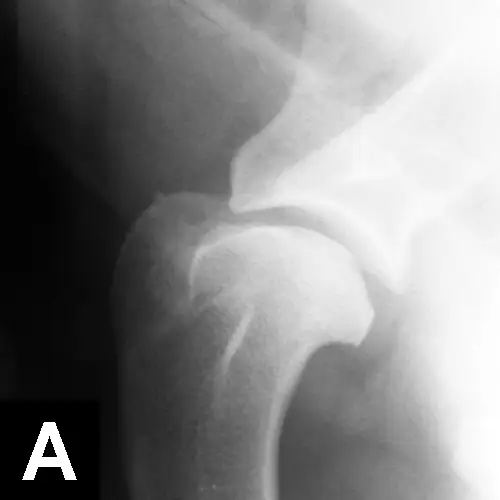

Figure 2. Postoperative ventrodorsal radiograph of the pelvis after triple pelvic osteotomy.

Case selection is important, as some factors (eg, age, subluxation and reduction angles, acetabular coverage of the femoral head) may affect the success of these procedures (eg, juvenile pubic symphysiodesis, triple pelvic osteotomy [TPO, Figure 2], double pelvic osteotomy [DPO]). Salvage procedures (eg, total hip replacement, femoral head and neck excision) are usually reserved for severe cases that do not respond to conservative treatment and are performed after growth has ceased.